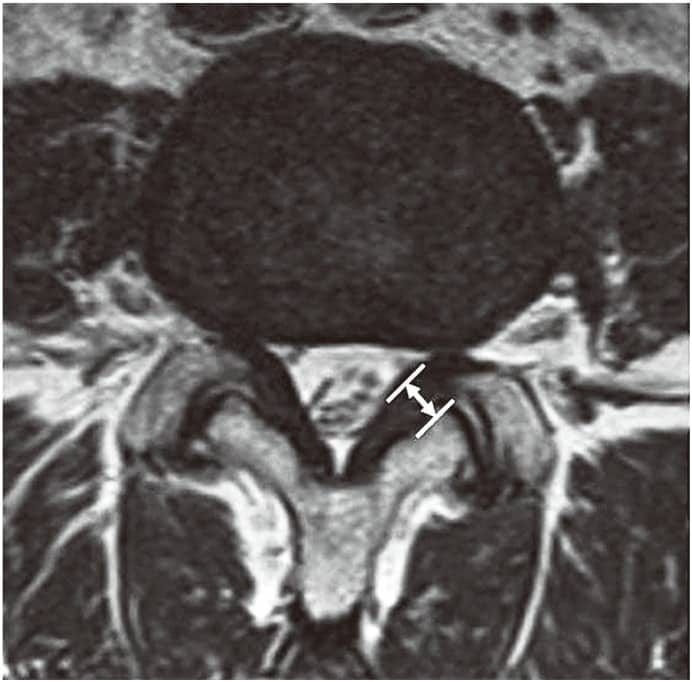

Ligamentum Flavum Kalınlaşması Nedir? Cerrahi Olmayan Tedavi Seçenekleri Bu makale, ligamentum flavum hipertrofisinin tanımı, nedenleri, belirtileri ve en iyi cerrahi olmayan seçenekler hakkında derinlemesine bilgi sunmaktadır. Fizyoterapi yöntemleri, ligamentum flavum hipertrofisini azaltabilir. Ligamentum Flavum Hipertrofisi Tanımlandı [...]

Boyun Fıtığı Belirtileri Nelerdir? Boyun fıtığı, tıbbi adıyla servikal disk herniasyonu, boyun bölgesindeki omurlar arasında bulunan disklerin zedelenmesiyle ortaya çıkan bir durumdur. Bu diskler, omurlar arasında yastıkçık görevi görür ve omurganın esnekliğini sağlar. Diskin dış bölgesindeki yırtılma sonucu iç kısımdaki [...]